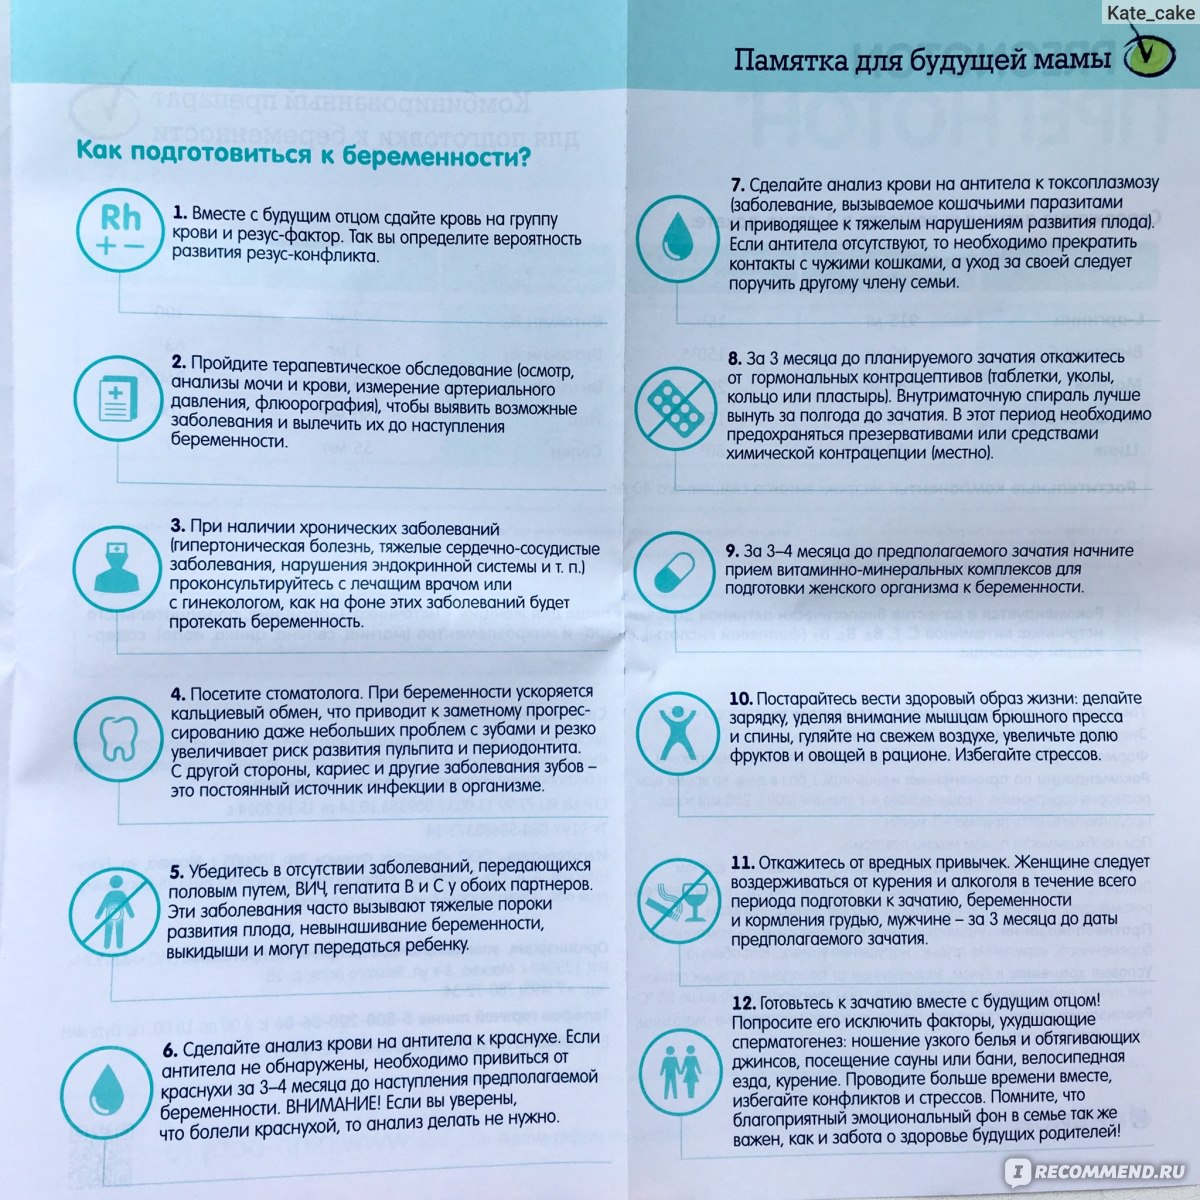

Рекомендации по зачатии